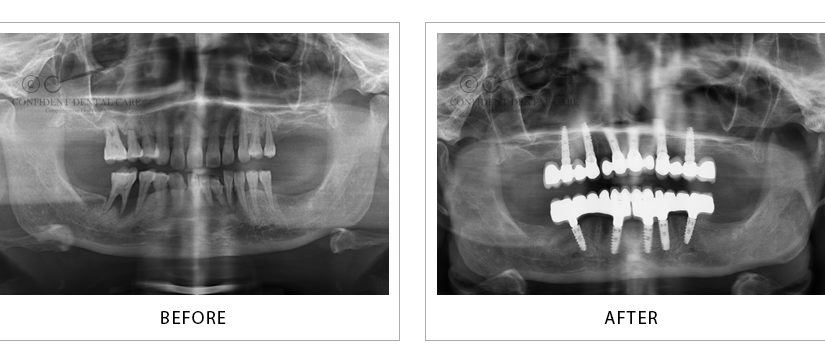

Implants X-ray